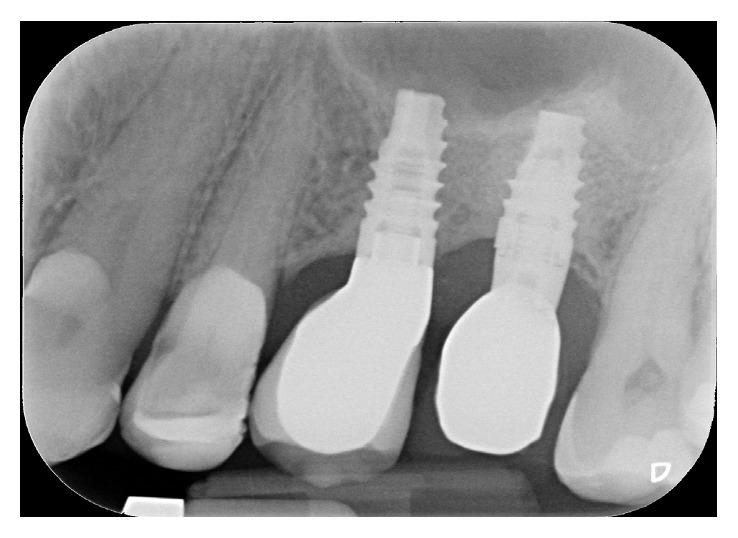

Tooth extraction is usually followed by bone reduction. In the maxillary posterior region, this remodelling combined with sinus pneumatisation and periodontal defects may lead to a reduced basal bone height available for implant placement. Sinus floor elevation can be performed with different surgical techniques. Crestal approach has demonstrated to be effective, less invasive, and associated with a reduced morbidity. This article reports a modified sinus floor elevation by means of rotary, noncutting instruments, addition of xenograft, and 2 short-threaded implant placements. The aim of the study was to evaluate the implant's success and intrasinus radiographical bone gain after 4 years of functional loading. The premolar implant site presented a starting basal bone height of 6 mm, while the molar site was of 2 mm. In the first surgical step, sinus floor elevation was performed mesially and the implant was inserted, and distally only sinus floor elevation was performed. After 6 months, the mesial implant was uncovered and the second implant was inserted; 4 months later, the second fixture was uncovered, and both fixtures were loaded with single provisional screw-retained crowns and later with single screw-retained porcelain fused to metal crowns. Implants integrated successfully, and crestal bone remodelling did not exceed the smooth collar. Bone gain was 3 mm for the mesial implant and more than 5 mm for the distal one.

拔牙后通常会出现骨量减少。在上颌后牙区,这种重塑加上鼻窦气化和牙周缺损可能导致可用于种植体植入的基骨高度降低。鼻窦底提升可以通过不同的手术技术来进行。牙槽嵴顶入路已被证明是有效的,侵入性较小,且发病率较低。本文报道了一种通过旋转非切割器械、添加异种骨移植材料以及植入两颗短螺纹种植体来改良鼻窦底提升术。本研究的目的是评估在功能负载4年后种植体的成功率以及鼻窦内的影像学骨增量。前磨牙种植位点的起始基骨高度为6毫米,而磨牙位点为2毫米。在第一步手术中,在近中进行鼻窦底提升并植入种植体,在远中仅进行鼻窦底提升。6个月后,暴露近中种植体并植入第二颗种植体;4个月后,暴露第二颗种植体,两颗种植体均安装单个临时螺丝固位冠,随后安装单个螺丝固位的烤瓷熔附金属冠。种植体成功整合,牙槽嵴顶骨重塑未超过光滑颈部。近中种植体的骨增量为3毫米,远中种植体的骨增量超过5毫米。